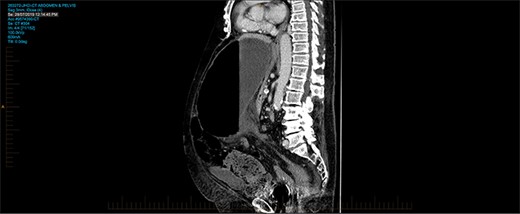

A 93-year-old patient who has history of recurrent sigmoid volvulus presented with a week of abdominal distension and bowels not working. Initial blood test revealed that she has white cell count 11.3 × 109/L, CRP 12 and lactate of 1.9. CT abdomen was performed on admission showed features of sigmoid volvulus. Patient was booked for flexible sigmoidoscopy to decompress the sigmoid volvulus. Flexible sigmoidoscopy revealed that there was significant mucosal necrosis of the sigmoid colon. A diagnostic laparoscopy was performed to determine the severity of necrosis. Laparoscopy reported that the sigmoid colon was oedematous but no signs of transmural necrosis. Patient was kept in the hospital for observation but there were no signs of improvement. Day 4 of the admission, patient continues to deteriorate clinically and had a medical emergency team response call for worsening pain and hypotension, and a repeat CT abdomen was performed. The images were consistent with sigmoid volvulus through transmesocolon defect resulting an internal hernia (Figure 5–7). The patient had emergency laparotomy. The sigmoid colon was found to be in the supracolic compartment and required decompression prior to reduction (Figure 1–4). There was transmural necrosis close to the rectosigmoid junction. Patient underwent Hartmann procedure. Patient recovered well postoperatively and discharged to home.

CT pm sagittal view showing sigmoid colon herniating through trasn-mesocolon defect.